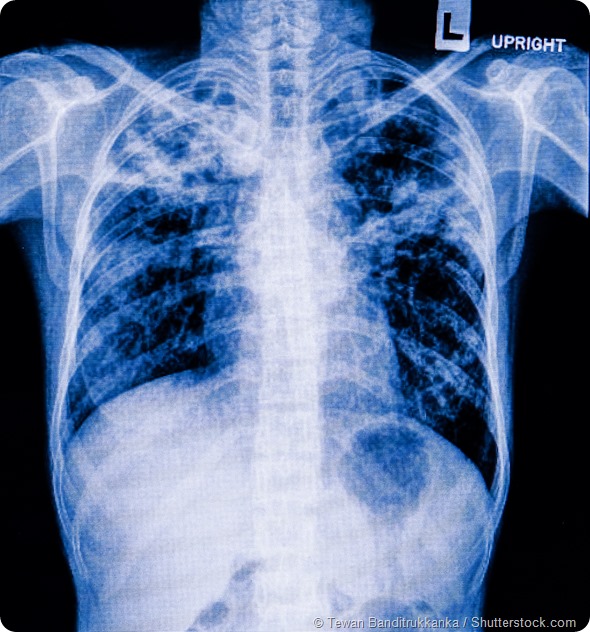

Pneumonia patients x-ray film